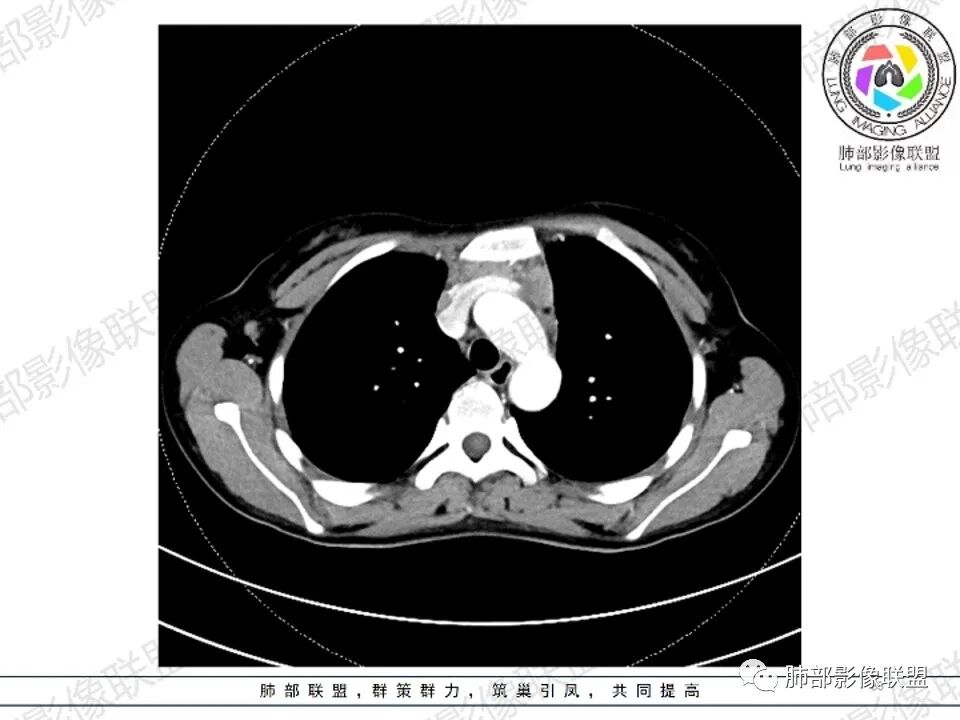

女,27,间断头晕、乏力3年,左眼视物模糊2月。贫血。胸部CT:前纵隔不规则肿块,多结节融合,边界不清,沿主动脉及肺动脉间隙生长,平扫密度欠均匀,增强扫描可见多发低密度坏死,纵隔血管供血穿行,腋窝多发大小不等淋巴结肿大。考虑恶性病变,胸腺癌?肉瘤?淋巴瘤?鉴别胸腺瘤、结节病等。

临床:年轻女性,慢性病程,多系统病变,头晕,贫血,视物模糊。

CT:定位纵膈病变,前中纵隔多发肿块,质软,塑形,密度不均匀,边界清楚。增强不均匀强化,坏死边界清楚,血管漂浮征。双侧腋下多组淋巴结肿大,明显异常强化。

考虑淋巴瘤可能。

鉴别诊断:系统性疾病,胸腺增生,胸腺瘤,胸腺癌